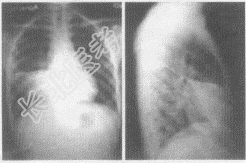

- 多项选择题2.患者行胸片正侧位检查,胸片图像表现如下, 你认为该患者应首先考虑哪些疾病

A、右肺中叶大叶性肺炎

B、右肺中叶肺癌

C、右肺中叶支气管扩张

D、右肺中叶结核

E、右肺中叶腺瘤

F、右肺中叶脓胸

D、右中下肺野形成一片密度增高的阴影,与右心缘相连,其上缘锐利平直,由此向下逐渐变淡,移行至正常透亮的肺野,肋膈角清晰

E、侧位片上呈三角形,尖端指向肺门,底部紧接前胸壁或肋膈角,上缘以横裂为界,下缘为斜裂的前半部